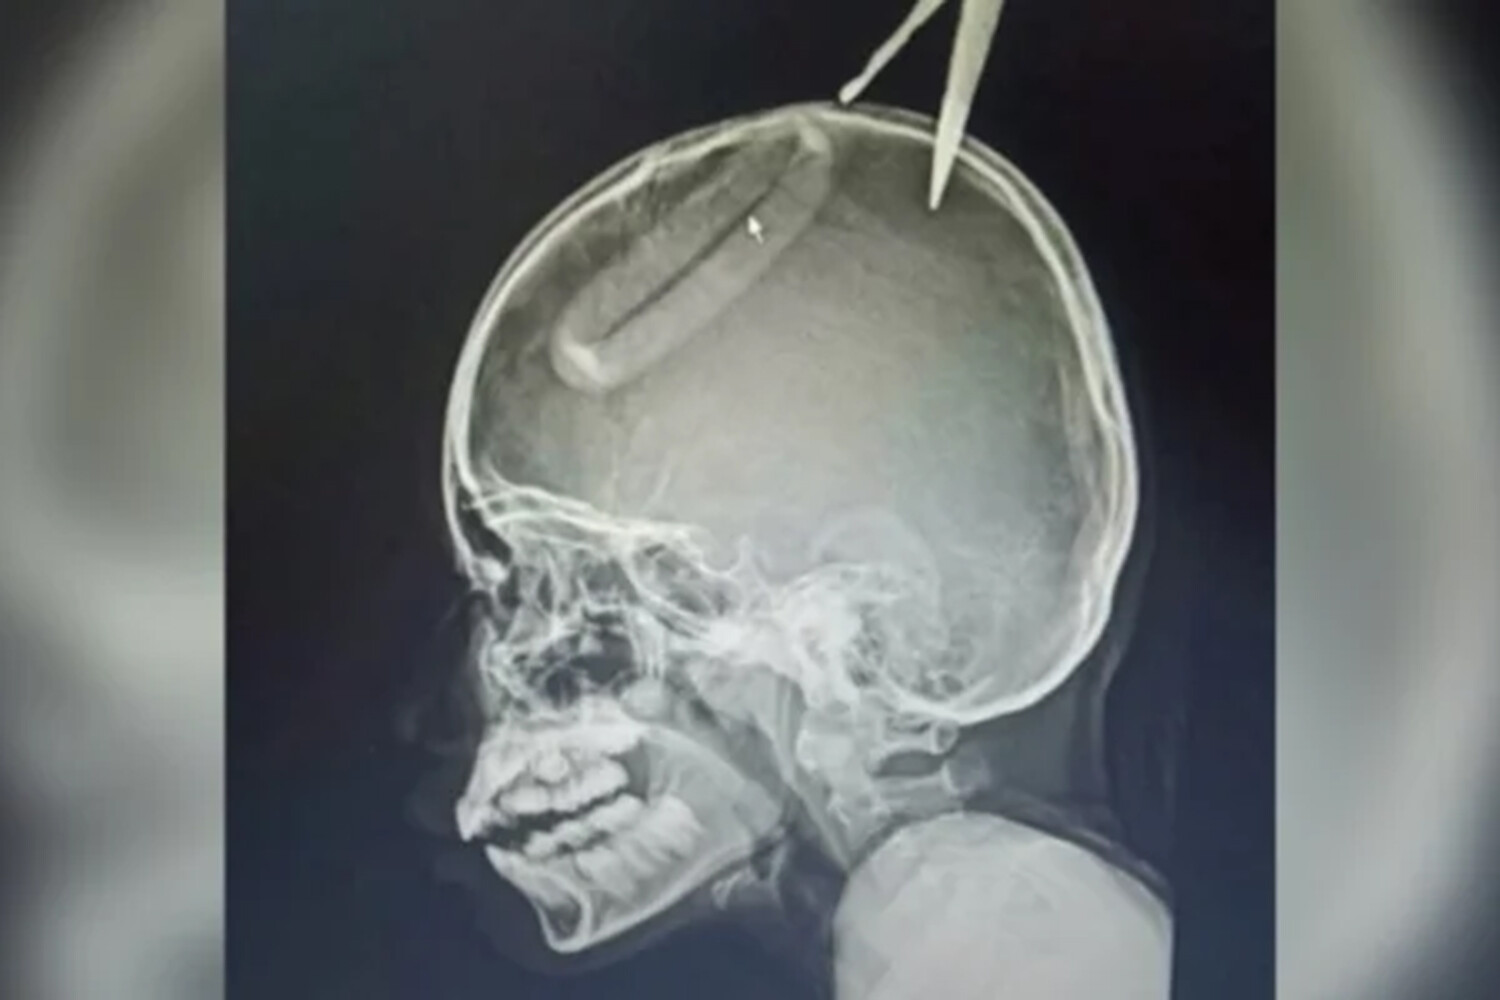

Одно из лезвий воткнулось в голову девочки, на помощь ей пришел дедушка, который находился в доме, пенсионер не смог самостоятельно вытащить ножницы из головы внучки.

Пострадавшую госпитализировали, врачи установили, что ножницы погрузились в череп на два с половиной сантиметра и едва не задели нерв. Несколько дней девочка провела в больнице и была выписана на амбулаторное лечение.